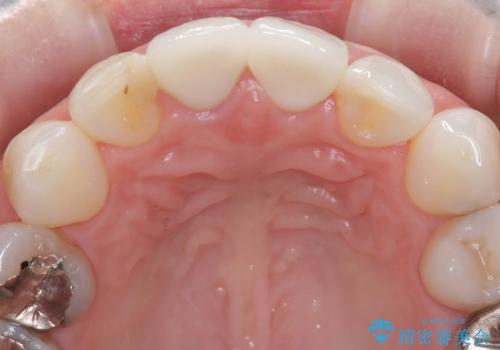

- [前歯の色が気になる」を主訴に来院された患者様です。歯の形を整えた後オールセラミッククラウンで治療を行いました。

以前他院にてセラミッククラウンを被せていたのですが、セメントの劣化なのか色が青白くなっていました。

歯の形を整えた後、色が透けないよう処置をしてオールセラミッククラウンで治療を行いました。